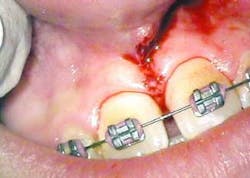

After infiltration of 1cc of local anesthetic solution, the Er:YAG laser (OpusDuo, OpusDent USA) was used at 350mj with a 1,000-micron, contact sapphire tip and heavy water spray to gently ablate the frenal attachment and underlying muscle tissue down to the level of the periosteum (figures 2, 3, and 4). Once this is accomplished, there is a small defect in the vestibular mucosa and interdental papilla where the frenal attachment and muscle once was. There is no charring, no burned tissue, and free bleeding in the site (figure 5).